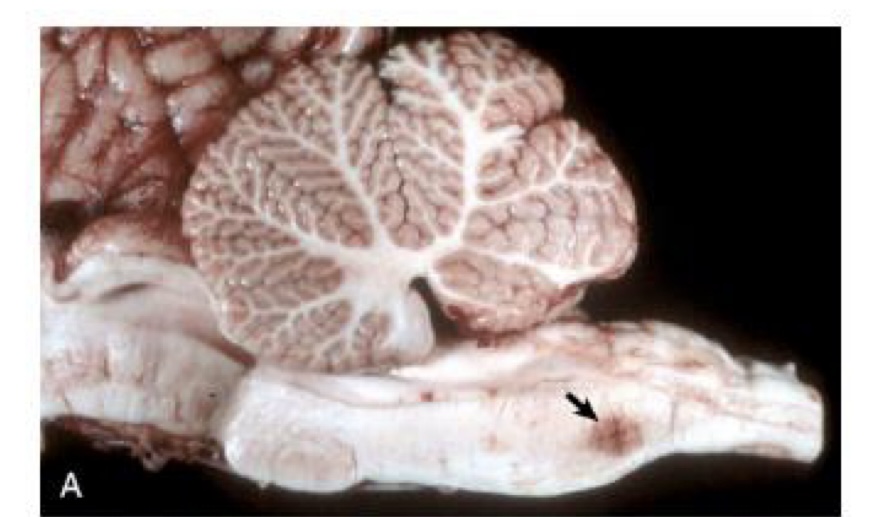

what is this?

oligodendroglioma → tumor is arising in a periventricular location and is gray, soft, and gelatinous

oligodendroglioma → tumor is gray, soft, and gelatinous